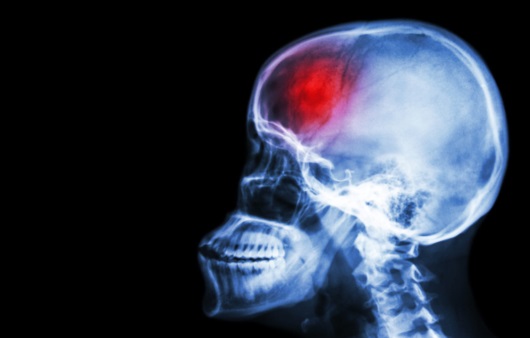

뇌졸중은 뇌 일부에 혈액을 조달하는 혈관이 막히거나 파열돼 뇌 손상을 발생시키는 질환으로 의식장애, 부분마비, 언어장애 등 각가지 신경학적 결함을 대동한다고 하고요. 뇌졸중은 뇌혈관 질환과 같은 말이며 우리나라에서는 중풍이라고 곧잘 말하고 있죠.

-두 번째는 뇌혈관 파열로 뇌에 혈액이 축적돼 그 부분의 뇌가 깨지거나 상하는 뇌출혈이나 출혈성 뇌졸중이고요.

6. 두통뇌혈관이 터지고 피가 나면 머리에 지나친 통증이 드러날 수있고요. 어쩌다 두통과 나란히 물을 마시는 것만으로도 속이 울렁거려요.